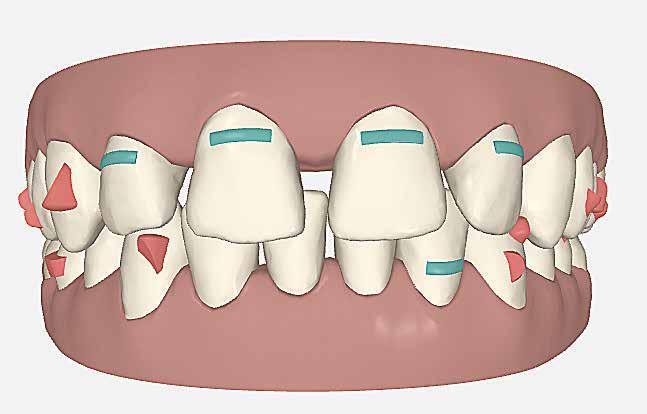

A szemfog oldalsó kismetsző helyére történő bemozgatása során a fog átalakítása javasolt a két fog eltérő morfológiai adottságai miatt (1. a-b. ábra). A fog kontúrozása, vagy úgynevezett formázása magába foglalja az approximális felszínek elcsiszolását, valamint a többi fogfelszín igazítását a kívánt fogformának megfelelően [1].

1. a–b ábra